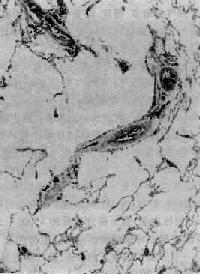

图9-11 慢性支气管炎 支气管粘膜上皮出现较多杯状细胞,固有层及粘膜下层内有慢性炎性细胞浸润,腺体呈粘液化 【临床病理联系】 患者因支气管粘膜的炎症和分泌物增多,而出现咳嗽、咳痰症状。痰一般呈白色粘液泡沫状。在急性发作期,咳嗽加重,并出现粘液脓性或脓性痰。由于支气管痉挛或支气管狭窄及粘液、渗出物阻塞而引起喘息。检查时,两肺可闻及哮鸣音、干湿啰音。有的患者因粘膜和腺体萎缩(慢性萎缩性支气管炎),分泌物减少,痰量减少甚或无痰。病变导致小气道狭窄或阻塞时,出现阻塞性通气障碍,表现为第1秒用力呼吸量和最大通气量明显降低,合併肺气肿时,肺残气量明显增多,肺总量也增大。 (二)肺气肿 肺气肿(pulmonary emphysema)是指呼吸细支气管以远的末梢肺组织因残气量增多而呈持久性扩张,并伴有肺泡间隔破坏,以致肺组织弹性减弱,容积增大的一种病理状态。在成人尸检例中,约50%可发现不同程度的肺气肿,其中约6.5%的患得因此病死亡。 【病因和发病机制】 肺气肿是支气管和肺疾病常见的併发症。与吸烟、空气污染、小气道感染、尘肺等关系密切,尤其是慢性阻塞性细支气管炎是引起肺气肿的重要原因。发病机制与下列因素有关: 1.阻塞性 通气障碍慢性细支气管炎时,由于小气道的狭窄、阻塞或塌陷,导致了阻塞性通气障碍,使肺泡内残气量增多,而且,细支气管周围的炎症,使肺泡壁破坏、弹性减弱,更影响到肺的排气能力,末梢肺组织则因残气量不断增多而发生扩张,肺泡孔扩大,肺泡间隔也断裂,扩张的肺泡互相融合形成气肿囊腔。 此外,细支气闭塞时,吸入的空气可经存在于细支气管和肺泡之间的Lambert孔进入闭塞远端的肺泡内(即肺泡侧流通气),而呼气时,Lambert孔闭合,空气不能排出,也是导致肺泡内储气量增多、肺泡内压增高的因素。 2.弹性蛋白酶增多、活性增高与肺气肿发生有关的内源性蛋白酶主要是中性粒细胞和单核细胞释放的弹性蛋白酶。此酶能降解肺组织中的弹性硬蛋白、结缔组织基质中的胶原和蛋白多糖,破坏肺泡壁结构。慢性支气管炎伴有肺感染、尤其是吸烟者,肺组织内渗出的中性粒细胞和单核细胞较多,可释放多量弹性蛋白酶。同时,中性粒细胞和单核细胞还可生成大量氧自由基,能氧化α1-抗胰蛋白酶活性中心的蛋氨酸使之失活。α1-抗胰蛋白酶乃弹性蛋白酶的抑制物,失活后则增强了弹性蛋白酶的损伤作用。 α1-抗胰蛋白酶由肝细胞产生,是一种分子量为45000~56000的糖蛋白,它能抑制蛋白酶、弹性蛋白酶、胶原酶等多种水解酶的活性。遗传性α1-抗胰蛋白酶缺乏是引起原发性肺气肿的原因,α1-抗胰蛋白酶缺乏的家族,肺气肿的发病率比一般人高15倍,主要是全腺泡型肺气肿。但是,在我国因遗传性α1-抗胰蛋白酶缺乏引起的原发性肺气肿非常罕见,并不重要。而最重要的也是最常见的是慢性阻塞性肺气肿(继发性肺气肿)。 【类型及其病变特点】 肺气肿病变发生在肺腺泡(acinus),即Ⅰ级呼吸细支气管所分布的肺组织范围内。属肺泡性肺气肿(alveolar emphysema)。根据病变的确切解剖部位及分布范围的不同可分为: 1.弥漫性肺气肿 (1)腺泡中央型肺气肿:腺泡中央型肺气肿(centriacinar emphysema)病变累及肺腺泡的中央部分,呼吸细支气管病变最明显,呈囊状扩张(图9-12)。而肺泡管、肺泡囊变化则不明显。 (2)全腺泡型肺气肿:全腺泡型肺气肿(panacinar emphysema)病变累及肺腺泡的各个部位,从终末呼吸细支气管直至肺泡囊和肺泡均呈弥漫性扩张,遍布于肺小叶内(图9-13)。如果肺泡间隔破坏较严重,气肿囊腔可融合成直径超过1cm的大囊泡,形成大泡性肺气肿(图9-14)。